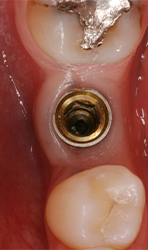

Maximum preservation of the alveolar housing and related gingival structures may be achieved following assisted atraumatic tooth extraction by an electrical mallet (Fig. 3).

Fig. 3

The aim of conservative implant surgery is to create a surgical site for implants by displacing a portion of native residual bone using blades and osteotomes pushed by Magnetic Max (Figs. 5a-5e).

The osteotomy is gradually expanded in 0.5 mm increments using osteotomes inserted to the working depth. The final diameter of the osteotomy is 1.2 mm less than the anticipated implant diameter, depending on local bone density.

Such mechanical sequence of osteotomes progressively condensed internal bone wall of initial hole radially outward with respect to central axis to create high-density bone tissue along a substantial portion of the length of the implant site preparation. The platform of the implants is inserted at the level of the alveolar crest. A minimum insertion torque of 30 Ncm is considered.